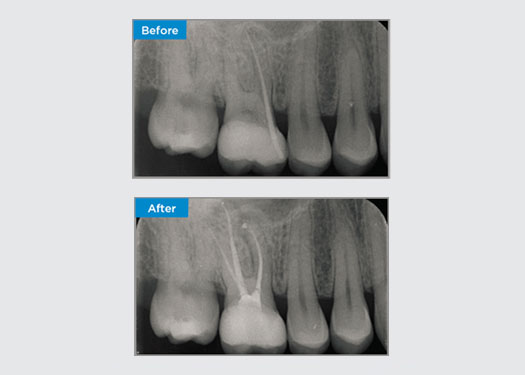

Der Patient stellte sich mit einer asymptomatischen apikalen Parodontitis an Zahn 34 vor. Auf dem präoperativen Röntgenbild war Zahn 34 mit zwei sichtbaren Wurzeln zu erkennen. Ein DVT-Scan bestätigte jedoch, dass es sich um einen dreifach verwurzelten Prämolaren handelte und dass sich die Kanäle in der Mitte der Wurzel in drei Kanäle aufteilten. Für diesen empfindlichen Zahn ist eine sorgfältige Feilenauswahl entscheidend.

Dr. Jack Lin, Endodontist, Sydney, NSW Australien

In dieser Situation ist die Erhaltung der Zahn-/Wurzelstruktur von entscheidender Bedeutung, um das Risiko von Vorsprüngen, Verschiebungen, Abrissen, Perforationen und Wurzelfrakturen zu verringern. Fallauswahl, Diagnose und Behandlungsplanung sind wichtig. Die Auswahl von endodontischen Feilen, die flexibel und effizient sind und die natürliche Wurzelanatomie respektieren, ist entscheidend.